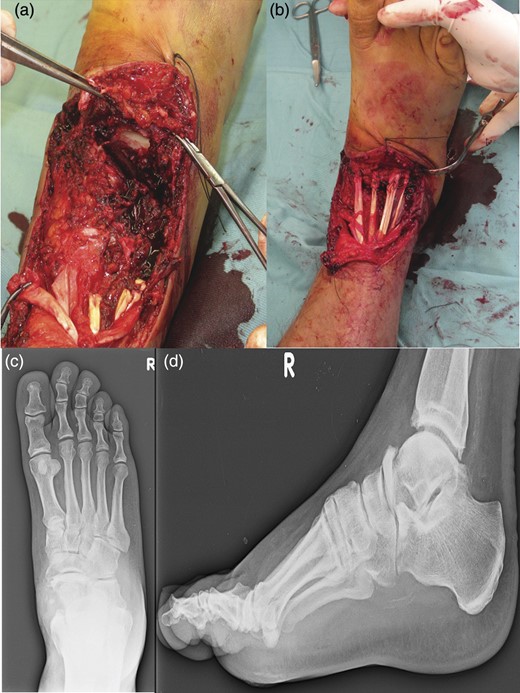

In August 2012, a 49-year-old-man presented to our hospital with a traumatic forefoot subamputation after a work accident. The trauma caused a lacerated wound in correspondence of the dorsal surface of the right foot. Radiographs and computed tomography (CT) examination confirmed the diagnosis of the loss of talus head during the trauma (Fig. 1).

AP (a) and lateral (b) radiographs and CT images (c, d) confirm the diagnosis of the loss of talus head during the trauma.